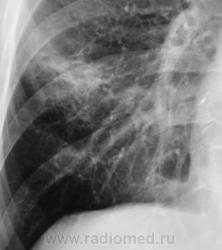

Первое исследование.